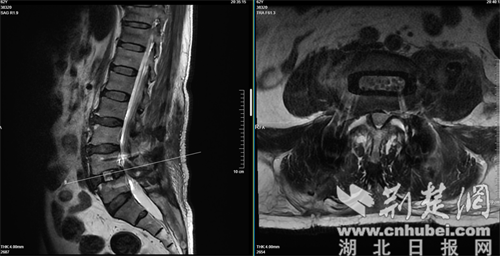

该技术通过人体腹侧肌肉的天然解剖间隙到达病变的椎间盘,不损伤腰椎后方的肌肉、韧带和骨骼结构。在麻醉科和手术室的密切配合下,主刀医生借助导航精准定位,沿腹侧外侧切口,逐层显露,精准放置通道,彻底摘除退变的髓核组织,处理好终板后,植入了填充了自体骨和异体骨的椎间融合器。术后透视显示,融合器位置理想,椎间隙高度恢复良好。

术后检测报告。通讯员 供图